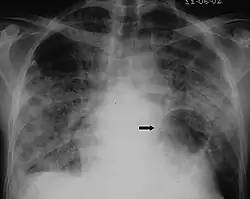

The diagnosis can be confirmed by the characteristic appearance of the chest X-ray and an arterial oxygen level (PaO2) that is strikingly lower than would be expected from symptoms. Gallium 67 scans are also useful in the diagnosis. They are abnormal in about 90% of cases and are often positive before the chest X-ray becomes abnormal. Chest X-ray typically shows widespread pulmonary infiltrates. CT scan may show pulmonary cysts (not to be confused with the cyst-forms of the pathogen).

-

Chest X-ray of increased opacification (whiteness) in the lower lungs. -

These chest radiographs are of two patients. Both show ground glass opacities. The left X-ray shows a much more subtle ground-glass appearance while the right X-ray shows a much more gross ground-glass appearance mimicking pulmonary edema.[7] -